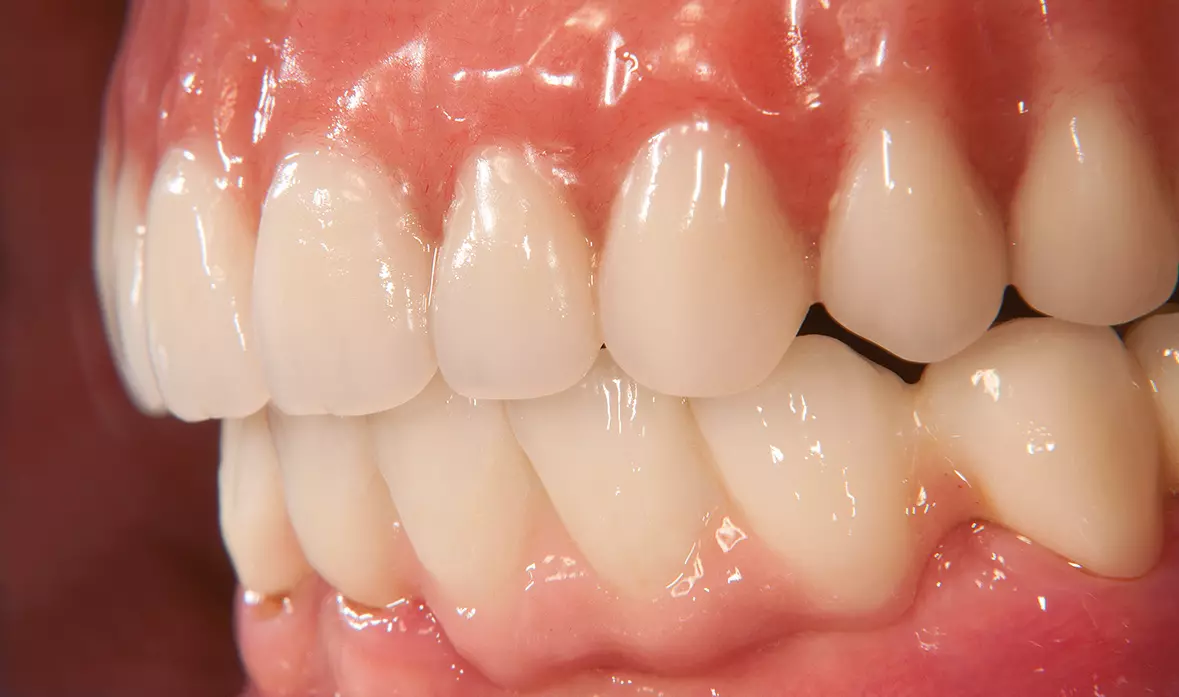

Abb. 45: Laterale Ansicht. Dr. Michael Leistner

Abb. 45: Laterale Ansicht.